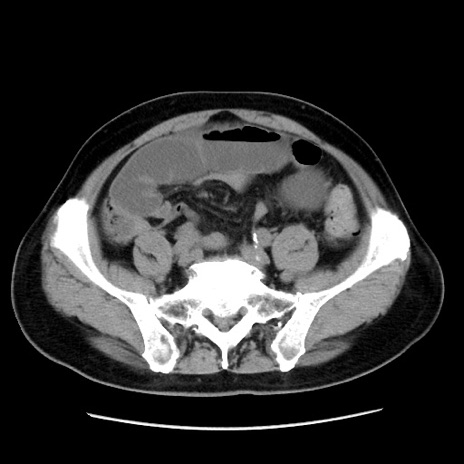

症例16(横断像)

【症例】 70歳代男性

【主訴】 腹痛、嘔吐

【現病歴】 約1ヶ月前より間欠的に腹痛と嘔吐あり、当院消化器内科を受診したところCTで多発する肝臓のLDAを指摘され、精査中であった。以降は消化器症状は安定していたが、2日前より嘔気と腹痛があり、同日より排便・排ガスが消失した。改善認めず、 本日、救急外来を受診した。

【既往歴】 大腸ポリープ切除後。

【身体所見】意識清明・会話良好、BT 36.3℃、BP 127/80mmHg、 P 80bpm、腹部:膨満あり、平坦・軟、上腹部正中および下腹部正中に圧痛あり、反跳痛なし、筋性防御なし。

【データ】WBC 7200、CRP 0.77